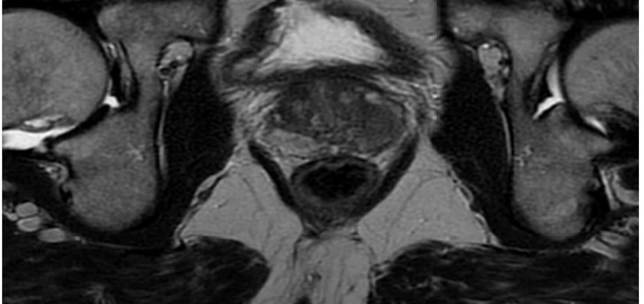

Paediatric Urology , Functional / Reconstructive Urology

Functional / Reconstructive Urology

Functional and reconstructive urology